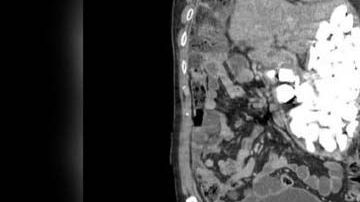

Paciente tenía dos kilos de piedras, tapas de botellas y monedas en el estómago por Redacción 20 de Febrero de 2019